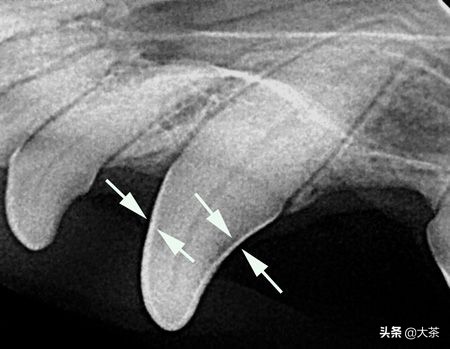

从X光片上可以清楚地看到牙釉质,由于密度高,它的颜色最白

这只猫咪断牙一年多,可以看到红点区域的牙根和骨骼已经被细菌感染破坏